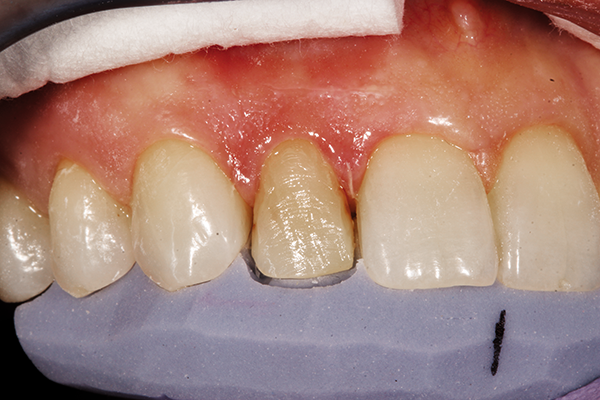

A patient with a very compromised cardiovascular condition wanted to conservatively improve her smile at tooth #7, where it was dark from retrusion and old compositematerial that was poorly shaped. To correct this matter, a strategy to whiten the surrounding teeth while a blueprint of an improved shape/volume was created on a model would be followed by gently reshaping line angles and doing a direct veneer on the challenging tooth (Fig. 6).

Fig. 6 Fig. 7

Tooth #7 was conservatively prepared to remove old composite buccally and interproximally. After microetching with aluminum oxide and rinsing with chlorhexidine, 37% phosphoric acid was applied and rinsed thoroughly with water and then lightly dried.